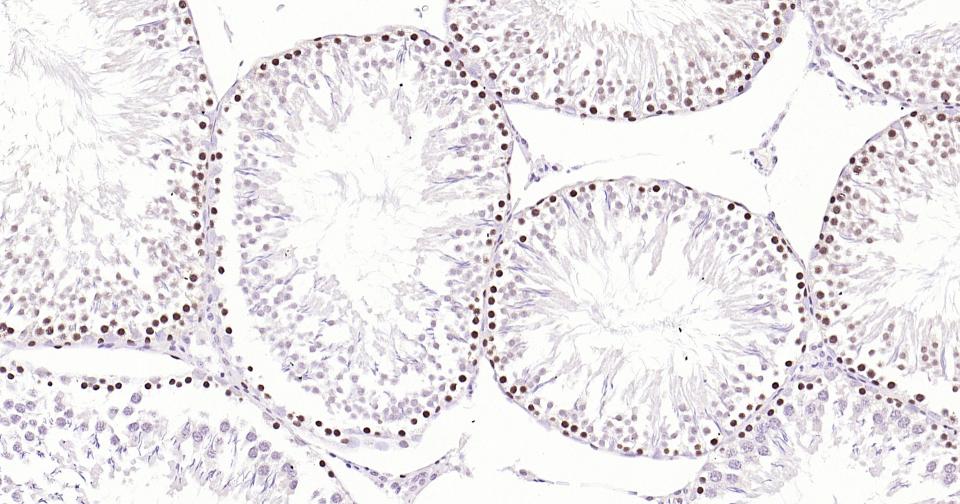

产品细节图片2

Paraformaldehyde-fixed, paraffin embedded Rat Testicles; Antigen retrieval by boiling in sodium citrate buffer (pH6.0) for 15 min; Antibody incubation with PCNA(Nuclear Loading Control) Monoclonal Antibody, Unconjugated(bsm-33035M) at 1:200 overnight at 4°C, followed by conjugation to the SP Kit (Mouse, sp-0024) and DAB (C-0010) staining.